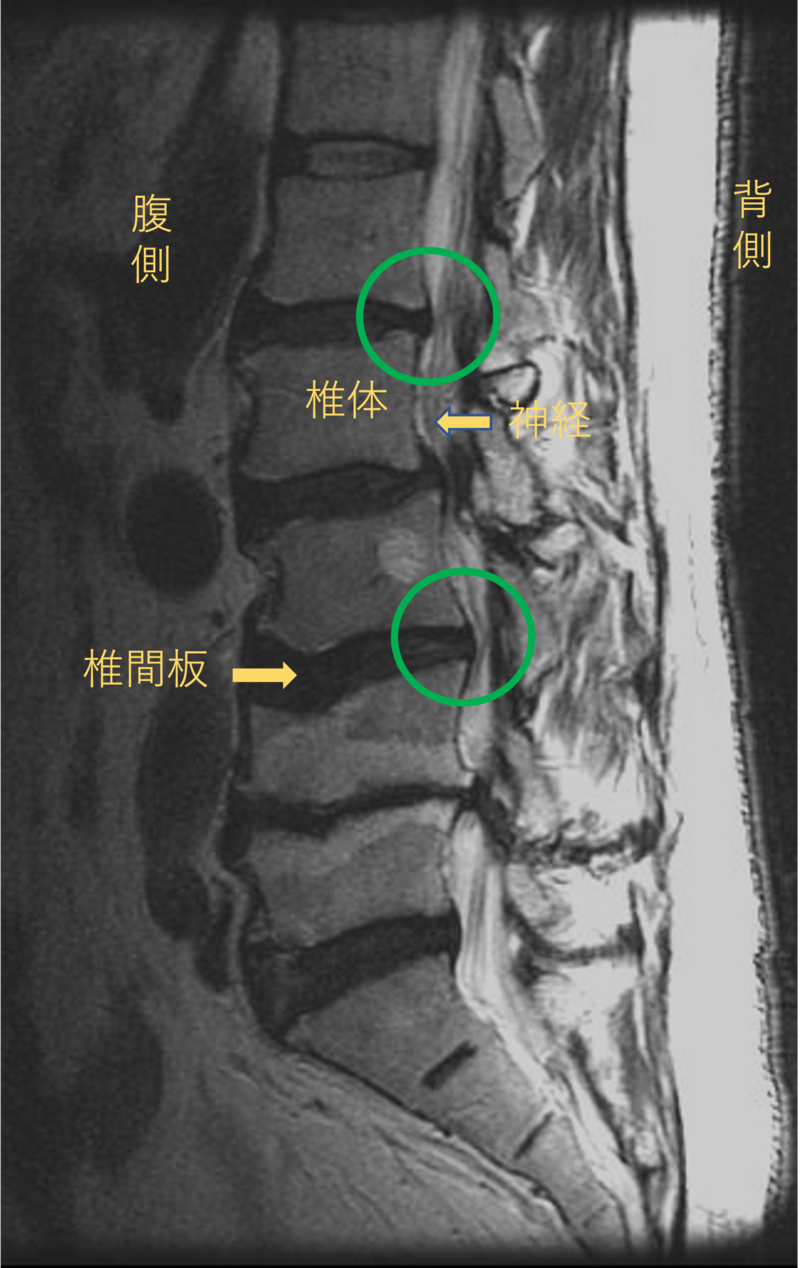

腰を横から見たMRI画像です。

腰椎という骨と骨の間に椎間板と呼ばれるクッションがあります。

このクッションの中身が飛び出す状態が椎間板ヘルニアと呼ばれます。

このMRI画像では、椎間板が背中側に飛び出して足に向かう神経が圧迫されることが痛みの原因となっておりました。